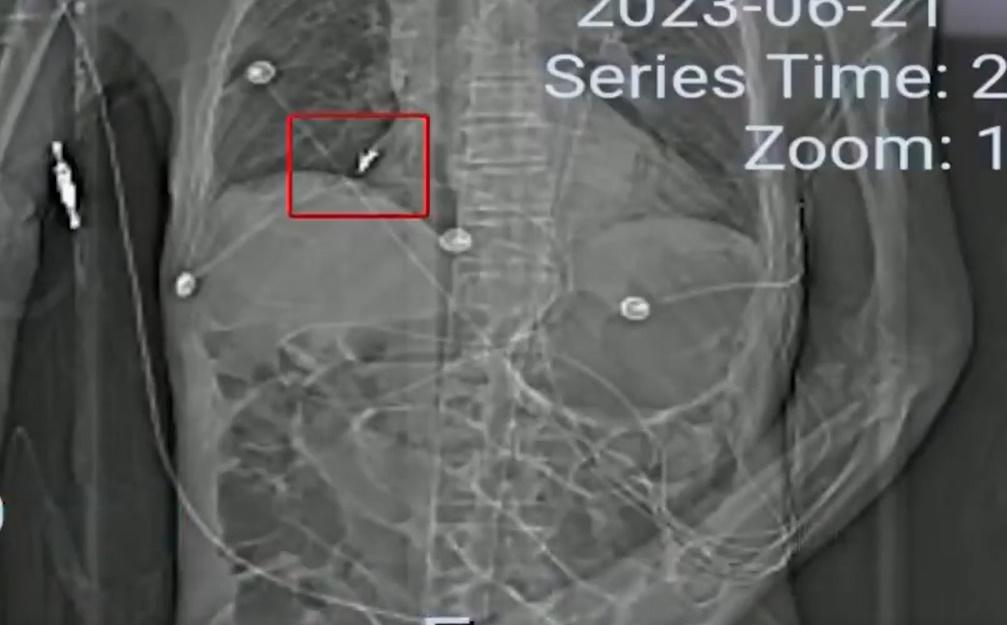

綜合報道,85歲姓孫的老翁,今年3月因胃口不好送院檢查,發現他消化道穿孔、重度貧血等疾病,第二日,院方為老翁進行手術,事後狀態亦好轉,不過,3月24日老翁突然出現了呼吸困難的狀況,院方為他做插喉,當天下午,老翁家屬到醫院ICU探病時,醫生將一隻牙齒交給他們,指是為老翁做氣管插管時發現。家屬認為肺裡的牙很可能會給老翁帶來致命性傷害,但牙齒為何會進入胸腹腔內。網上影片可見,醫院表示,老人在住院期間確實做了多次氣管插管,在插管前,醫務人員已對老人的牙齒做過相關檢查。詎料20日後,醫院又在父親的胸腹腔內發現了6隻牙齒和一個牙套。家屬表示,直到4月14日做支氣管鏡時,發現肺裡有一隻牙,再調查後在食道下端,快進入胃的地方又發現了5隻牙和一個牙套。

醫生表示,老翁肺部的假牙形狀特殊,有鈎子,院方做了各種嘗試,最終都未能取出,另外,經過醫院治療,老翁胃部的狀況明顯得到了好轉,隨後就轉入了普通病房。不過沒多久,老翁出現了胃出血的情況,同時高燒不斷,肺部反復出現感染,直到老翁臨終,肺裡的牙都未取出。家屬指,自從牙齒進入肺部以後,老翁的肺部就一直有炎症,高燒不斷,院方也一直在想辦法把牙齒取出,過程中不僅加重家屬的經濟負擔,還讓老人家受罪。院方提出給予50萬元人民幣作不做醫療鑒定的補償,家屬則指,老翁住院期間不算醫保,自費已花掉逾30萬元,其中部分費用用於取牙齒及治療肺部怠染,認為補償金額無法接受。目前,雙方仍就補償金額協商。